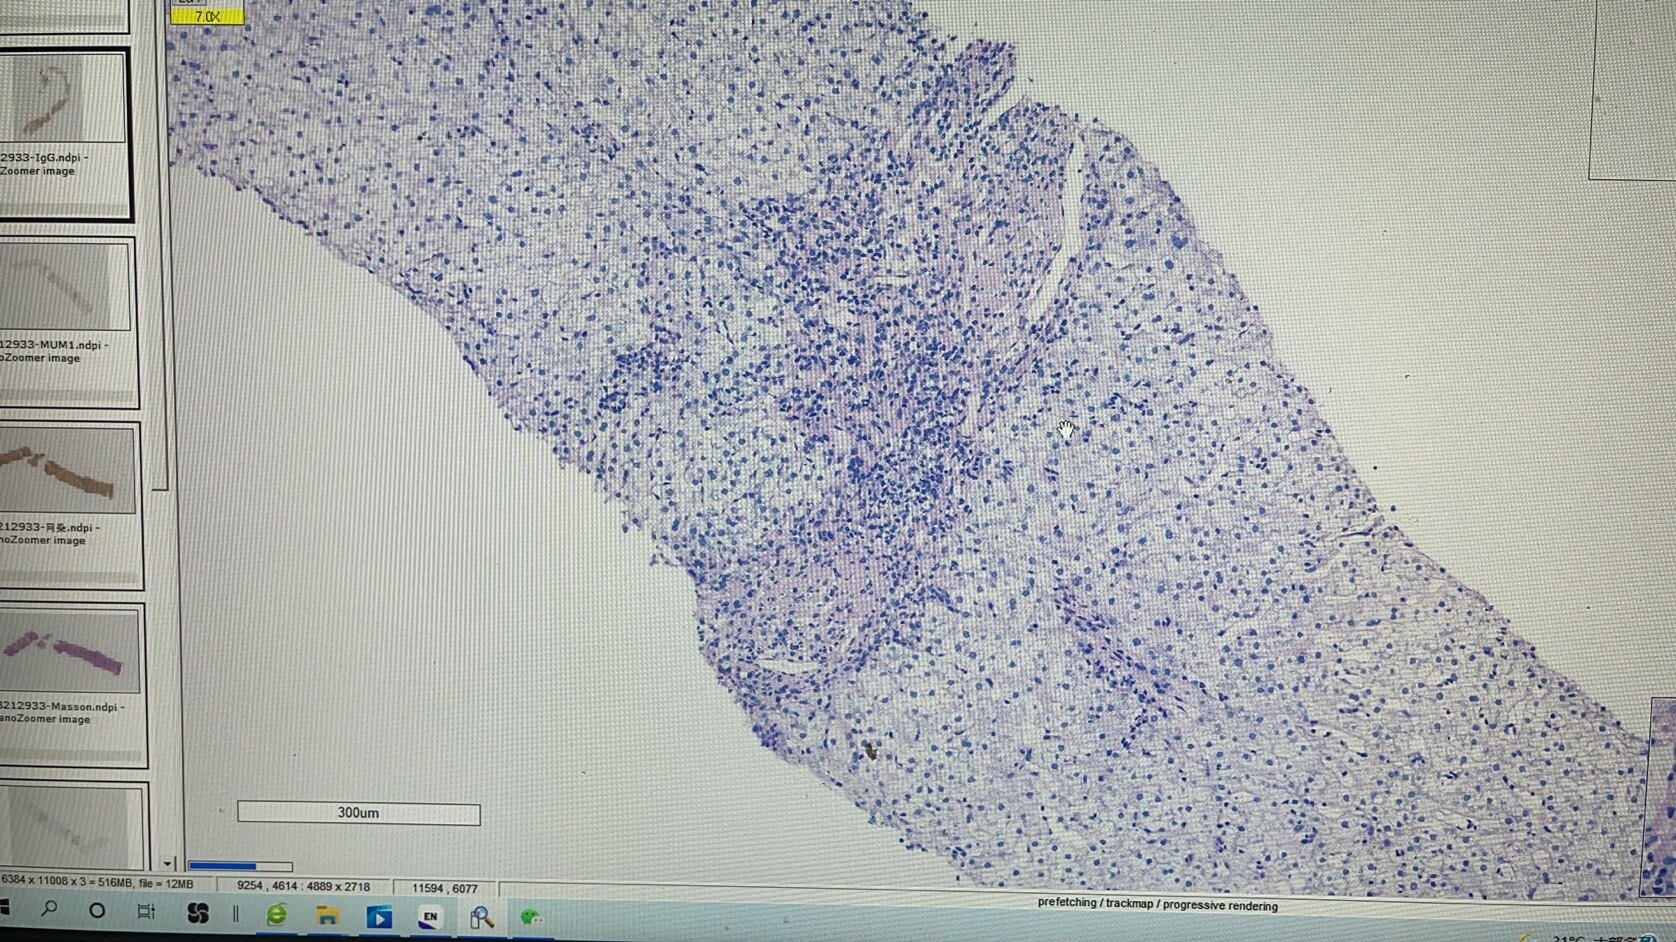

肝活检的意义

经常碰到长期肝功能异常的患者,常规检查做了仍不能找到原因。这时候我会建议进行肝活检,虽然有时候肝活检仍然不能给予一个确切的诊断,但是起码能够知道病变的部位在哪?是肝细胞损伤为主,胆管损伤为主,还是两者兼有,这样我们就能根据不同的患者给予不同的治疗方案,做到精准治疗和个体化治疗!